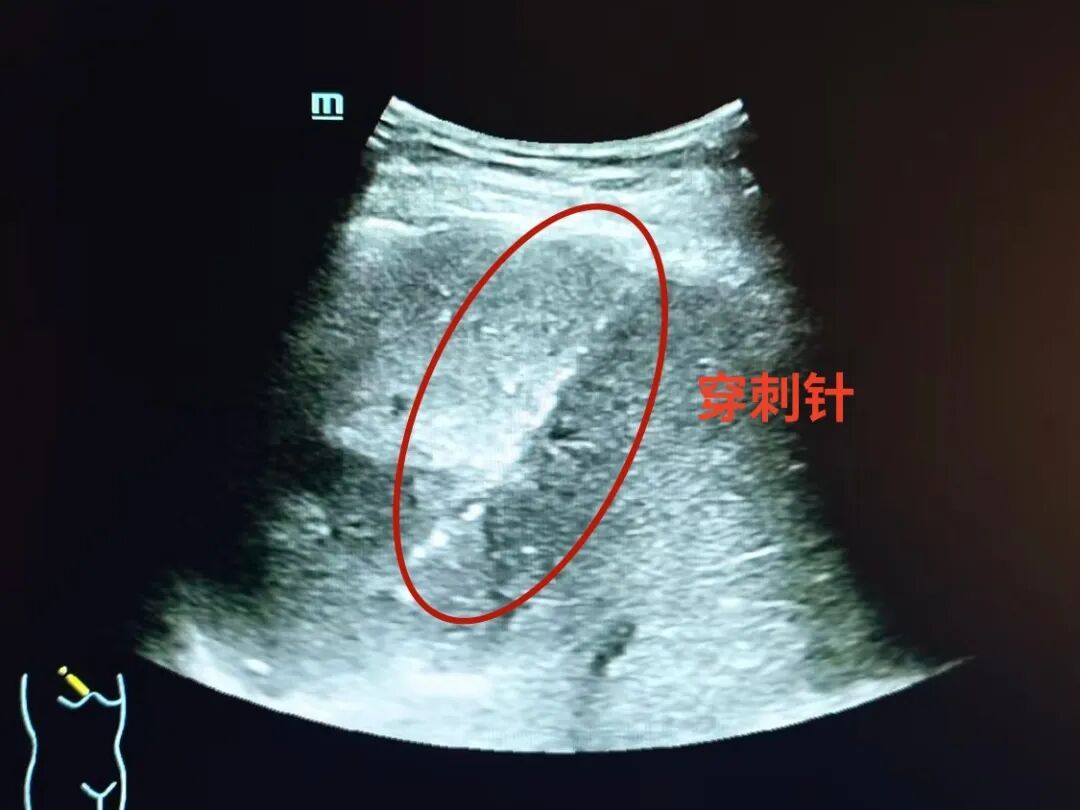

经过充分研讨,两人一致决定为黄阿姨实施 超声引导下肝脓肿穿刺置管引流术 ——这种“以针代刀”的微创疗法,能在实时影像引导下精准避开血管和重要脏器,仅用细针穿刺就能置入引流管,把脓液直接引出来,再配合药物治疗,既安全又高效。

在与患者及家属充分沟通治疗方案、消除其顾虑后,手术顺利开展。石俊泰主任凭借丰富的超声介入经验,在实时影像“导航”下精细操作,精准将细针穿刺进入脓肿部位,顺利引出脓液。整个手术耗时不到20分钟,术中患者无明显不适。